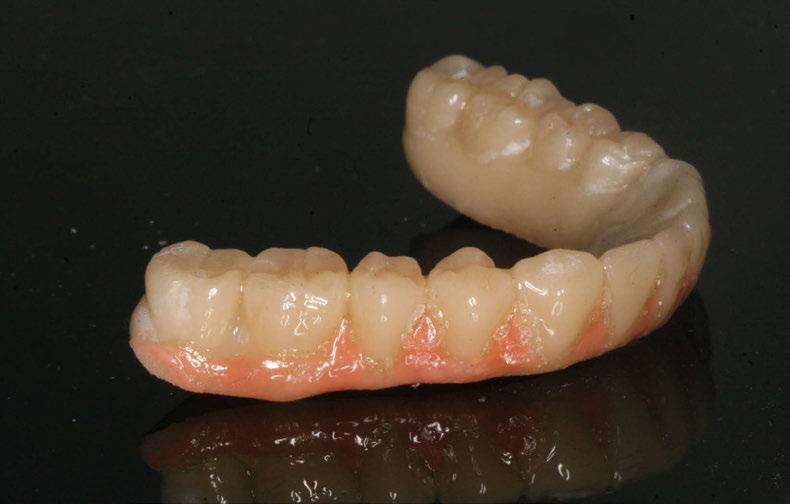

SW 5.2, Dentsply Sirona) (Figuras 22-27), la cual fue materializada en dos tipos de materiales a partir de bloques cerámicos IPS Empress CAD y cerámica vítrea de disilicato de litio IPS E.max CAD (Figuras 28-30)

Figura 30. Restauracones impresas vista oclusal superior e inferior. Figura 29. Prueba de las restauraciones en modelo impreso en 3D. Figura 28. Bloques de IPS Empress CAD fresados. Vista frontal.